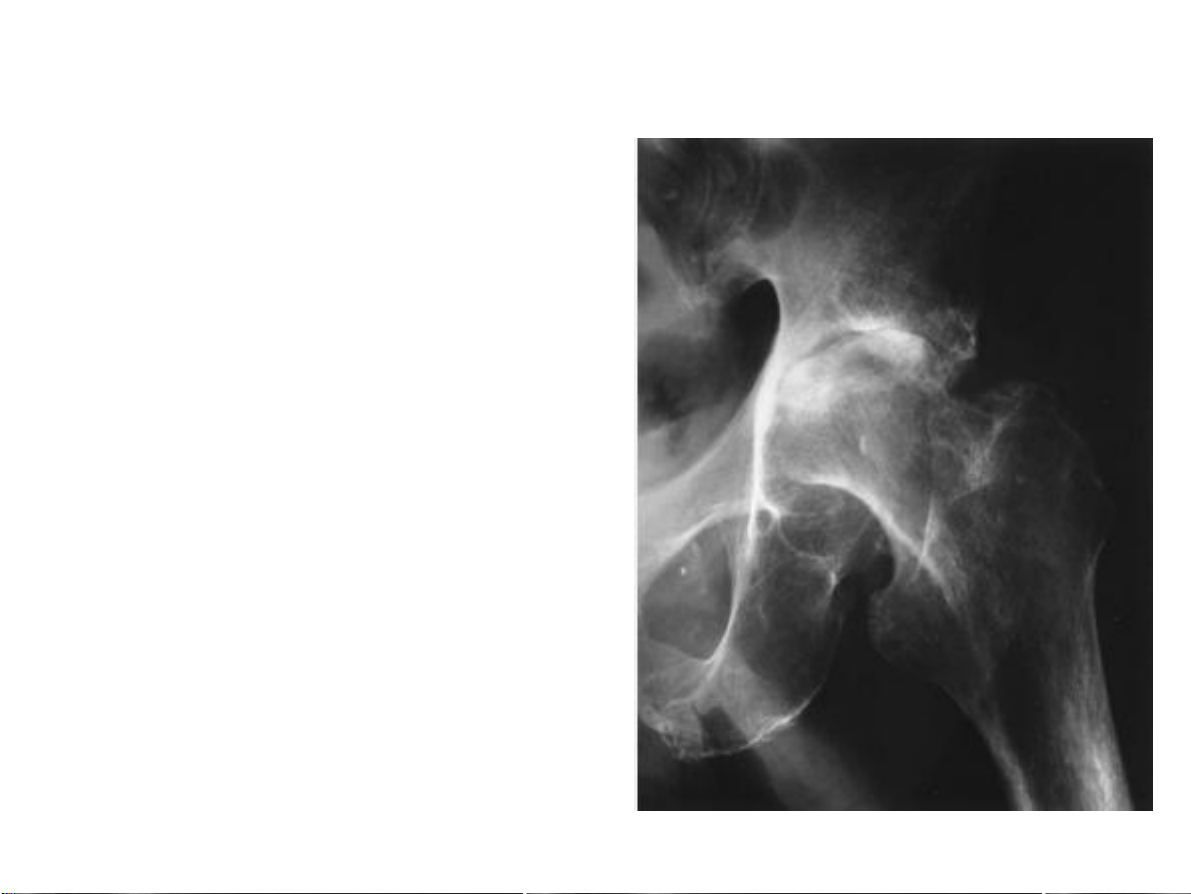

Hai ví dụ của quá trình tân tạo xương. Phản ứng đặc xương ở chỏm

xương đùi và mái ổ cối trong thoái hóa khớp háng (hình A). Đặc xương

lan toả ở cột sống thắt lưng, xương cùng và xương chậu hai bên trong di